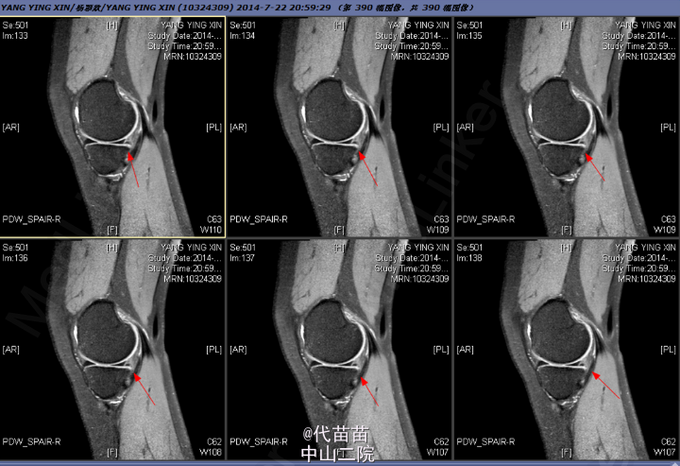

患者女,27岁,因扭伤后右膝关节不适2月余入院。

右膝关节麦氏征(+),蹲走试验(-),过伸试验(-),过屈试验(-),浮髌征(-),髌骨加压研磨试验(-),前抽屉试验(+),后抽屉试验(-),侧方应力试验(-),lachman征(+),关节活动度0-135度,股四头肌无明显萎缩,肌力正常;肢端血运、感觉、活动正常。

诊断: 1.右膝关节前交叉韧带损伤;2.右膝关节半月板损伤 行右膝关节镜检,前交叉韧带重建,内侧半月板修补术